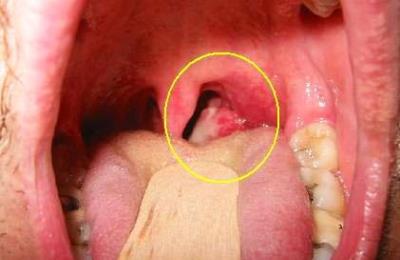

Абсцессы, располагающиеся за глоткой, паратонзиллярноили в области надгортанника тоже объясняют комок.

В этом случае слизисто-гнойная полость, развитие которой может быть спровоцировано, например, недавно перенесенной ангиной, также перекрывает вход в гортань. А белые комочки служат признаком тонзиллита. При этом часто человек отмечает боль при глотании.